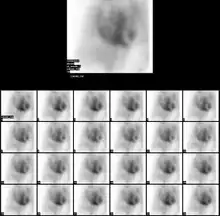

Normail MUGA scan | |

The patient is placed under a gamma camera, which detects the low-level 140 keV gamma radiation being given off by Technetium-99m (99mTc). As the gamma camera images are acquired, the patient's heart beat is used to 'gate' the acquisition. The final result is a series of images of the heart (usually sixteen), one at each stage of the cardiac cycle.

The resulting images show that the volumetrically derived blood pools in the chambers of the heart and timed images may be computationally interpreted to calculate the ejection fraction and injection fraction of the heart. The Massardo method can be used to calculate ventricle volumes. This nuclear medicine scan yields an accurate, inexpensive and easily reproducible means of measuring and monitoring the ejection and injection fractions of the ventricles, which are one of many of the important clinical metrics in assessing global heart performance.